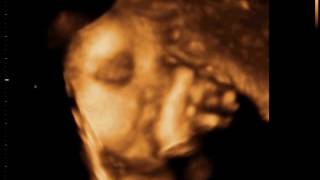

Ellyza Ultrasound12

Ellyza Ultrasound18

Ellyza Ultrasound13

Ellyza Ultrasound8

Ellyza Ultrasound23

Ellyza Ultrasound9

Ellyza Ultrasound2

Ellyza Ultrasound5